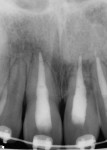

The patient, who was then asymptomatic, presented 10 days later (20 days post-trauma). Upon examination, teeth Nos. 8 and 9 were tender to percussion and palpation, while tooth No. 10 was not tender. Teeth Nos. 8 and 9 were nonresponsive to thermal testing, while tooth No. 10 was responsive. Tooth No. 8 was +1 mobile, while tooth No. 9 remained +3 mobile. Radiographically, tooth No. 8 had an intact lamina dura except for the apical portion, which was due to persistent extrusion. Tooth No. 9 exhibited a widened periodontal ligament space (Figure 7). Local anesthetic with epinephrine was administered via buccal infiltration and an incisive canal block. Teeth Nos. 8 and 9 were isolated individually with a rubber dam for endodontic treatment. The rubber dam and the individual tooth were disinfected with 70% isopropyl alcohol. The rubber dam was sealed with OraSeal® (Ultradent Products, Inc., www.ultradent.com). Nonsurgical treatment was performed under magnification with a Zeiss Opmi® pico surgical operating microscope (Carl Zeiss Meditec, www.zeiss.com). Nonsurgical treatment of each tooth consisted of a standard endodontic access, biomechanical instrumentation with stainless steel hand files, Gates-Glidden burs 3-6, as well as Protaper and Profile Series 29 nickel titanium rotary instruments (all from DENTSPLY).

Upon access, both teeth were determined to have pulpal necrosis without signs of intracanal fracture. The teeth were alternatively irrigated with copious amounts of 6% sodium hypochlorite (NaOCl) (Clorox® Bleach, The Clorox Company, www.thecloroxcompany.com) and 17% ethylenediaminetetraacetic acid (EDTA) (Vista Dental, www.vista-dental.com). Canal length estimation was determined with a Root ZX® apex locator (Morita, www.morita.com). Final length was verified radiographically with a trial gutta percha point. The teeth were soaked and irrigated with MTAD per manufacturer’s recommendation (DENTSPLY). Canals were then dehydrated with 70% isopropyl alcohol (American Dental Supply,www.americandentalinc.com ). Obturation was completed (Figure 8) with gutta percha (DENTSPLY), and Pulp Canal Sealer EWT (SybronEndo, www.sybronendo.com), using a continuous wave technique with thermoplasticized backfill using System B (SybronEndo) and Calamus (DENTSPLY) units, respectively. The access openings were etched with 37% phosphoric acid (Benco Dental, www.benco.com), primed and bonded (ClearFil Bond), and restored with Geristore (DenMat, www.denmat.com). The accesses were polished and the occlusion adjusted.